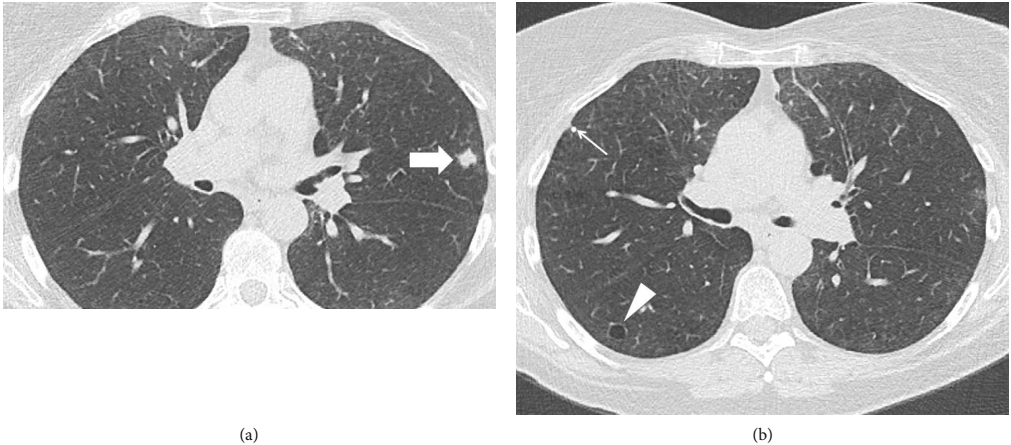

63岁女性患者,吸烟,有15包/年的吸烟史,在另一家医院接受肺部LDCT检查以评估和处理一个肺部结节。LDCT胸部显示左上叶11 mm结节,边缘有毛刺。其他影像学特征包括上叶为主的小叶中心气肿,一些微小的钙化结节,可能是陈旧性肉芽肿,以及两个小的薄壁囊肿(图1)。患者按照建议完成了全身PET/CT扫描。PET/CT扫描显示结节具有(18)F-氟脱氧葡萄糖(FDG)的亲和力,标准摄取值(SUV)为4.2(图2),身体其他部位无异常摄取。患者的症状包括偶尔咳嗽,否认有明显的呼吸急促、发烧、发冷、盗汗、体重减轻及咯血等症状。

结节,1.1 cm,,边缘有毛刺(箭头),右下叶薄壁实质囊肿(箭头),右上叶一个微小的钙化结节(细箭头)。左上叶不规则形状图1. (a,b)胸部CT轴位图像显示